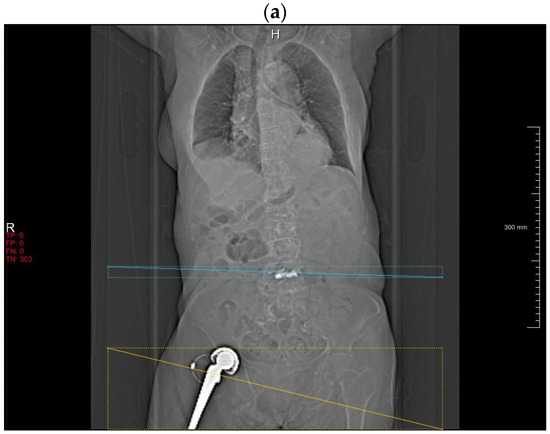

With abdominal CT topograms, the DLA frequently misclassified vertebroplasty cements (n = 6) as metallic spine implants (Figure 2a). Residual barium in the transverse colon (n = 1), chemoport (n = 1) and external metallic structures outside the body (n = 2) were other causes of false-positive classification.

Figure 2.

Falsely interpreted cases by the DLA. Bone cement in the spine is misinterpreted as spine implant (a). Sacroiliac extension of the spinal instrumentation is misinterpreted as hip implant (b). Non-conventional spinal implant (arrow) without typical rod-screw system is not detected (c).

With spinal CT AP and lateral topograms, the leading cause of misclassification by the DLA was sacroiliac extension of the rod-screw systems, the majority of which were interpreted as hip implants, rather than components of spine implants (n = 21) (Figure 2b). Generators (n = 2), proximal rods (n = 2) and penile implants (n = 2) follow as false-positive classification sources.

Most of the detection failure by the DLA occurred when there was no classic rod-screw instrumentation system (Figure 2c). In addition, the DLA did not detect any hip implants in lateral topograms.